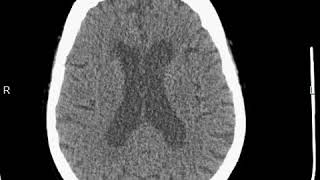

К клинике, диагностике и патогенезу субарахноидального кровоизлияния : Автореферат дис. на соискание учен. степени кандидата мед. наук

Берзиньш Ю.Э. К клинике, диагностике и патогенезу субарахноидального кровоизлияния : Автореферат дис. на соискание учен. степени кандидата мед. наук / М-во здравоохранения Латв. ССР. Риж. мед. ин-т. - Рига, 1957. - 19 с. : ил. ; 22 см

Субарахноидальное пространство → Кровоизлияния